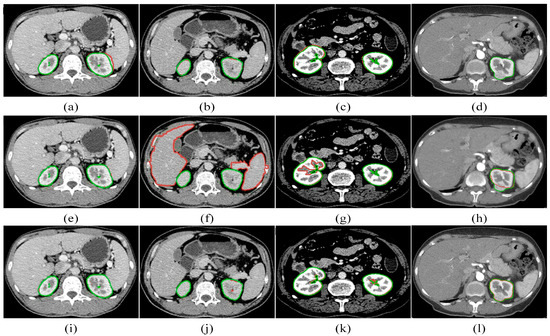

To demonstrate the high performance of our kidney segmentation framework, we compare our proposed method with the multi-atlas [35] and kernel graph cuts (KGCs) [36]. For the KGC experiment, the K-Means cluster result is utilized to construct the graph and perform the postprocessing of the filling operation to achieve the best possible results. Figure 14 depicts the kidney segmentation results of four kidneys, where the three rows indicate the corresponding segmentation results of the multi-atlas method, the KGC method, and the proposed method, respectively. The manual ground truth is shown in green, while the segmentation result is in red. From Figure 14a, it can be observed that the multi-atlas method fails to segment the right kidney and the right kidney is over-segmented. The KGC method, as seen from the results, has over- or under-segmentation problems. Additionally, it could not handle low-contrast images, as demonstrated in Figure 14f, and the intensity inhomogeneity of kidneys, particularly the renal medulla, which is not surrounded by the cortex (see Figure 14g). For kidneys with tumors, the multi-atlas method fails to segment the entire kidney, as shown in Figure 14d, and the KGC method cannot segment the tumor part, as shown in Figure 14h. In comparison, our method accurately segments not only the healthy kidneys but also the tumors, as shown in Figure 14l. In comparison with the multi-atlas method and the KGC model, our proposed approach could segment kidneys accurately.

Figure 14. Comparative segmentation results of four randomly chosen CT slices for the multi-atlas [34] (ad), the KGC [35] (eh), and the proposed approach (il). The segmentation result is shown in red, while the manual ground truth is shown in green.